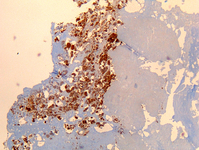

Coxiella burnetii chronic hepatitis of a patient with endocarditis: immunohiostochemistry. Note the absence of doughnut granuloma seen in acute Q fever. Brown coloration identifies bacteria in monocytes/macrophages

Hubert Lepidi, Institut Hospitalo-Universitaire Méditerranée Infection